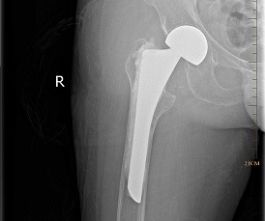

完成手術(shù)準(zhǔn)備后,4月4日由喻燦明副主任中醫(yī)師主刀行“右人工股骨頭置換術(shù)”。(術(shù)后復(fù)查片見圖2)

- 圖 2 -